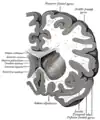

Coronal section through anterior cornua of lateral ventricles. Coronal section through anterior cornua of lateral ventricles.

Coronal section of brain through anterior commissure. Coronal section of brain through anterior commissure.